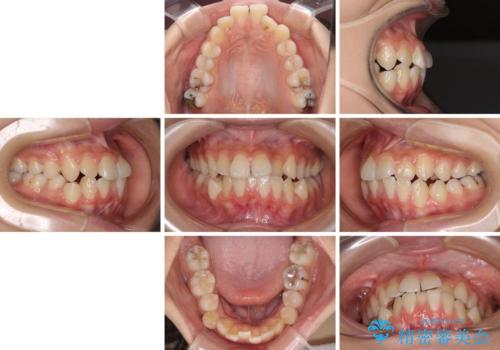

- 下顎の前突感と前歯の叢生を気にして来院された患者様です。

下顎前方位の骨格のため、下顎歯列に対して上顎歯列の幅が狭くなっていました。

急速拡大装置を用いて上顎骨を側方に拡大し、上顎の叢生を解消するとともに下顎歯列拡大により下顎の叢生も解消することとしました。

急速拡大装置使用直後は著しいスペースが正中に発現するため、ワイヤー矯正を行いますが、今回は治療期間を短くしたいとのことで、上下全体をワイヤー装置にて矯正治療することとしました。